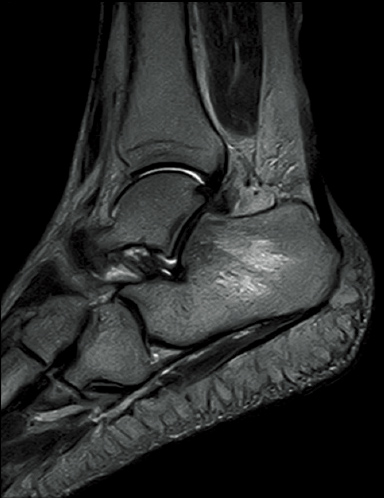

FatSat-PDWI

T2WI